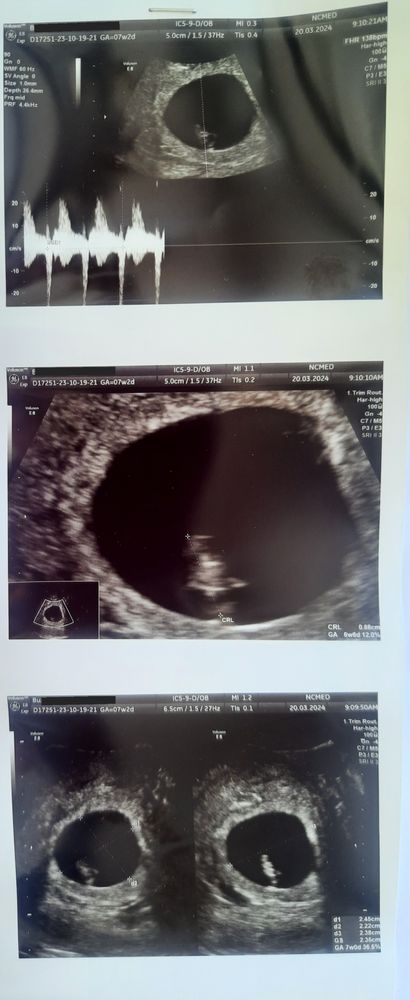

УЗИ 7+2, 30дпп

Я БЕРЕМЕННА !Сходила сегодня на УЗИ. 🥹 Креветонька растёт, сердечко бьётся. Плодное яйцо красиво круглое, в отличие от прошлых визитов. Срок акушерский 7+2, скорректированный по переносу 7 недель ровно. 30 дней после переноса. Очень волновалась после прошлого быстрого УЗИ, не выдержала и пошла с мужем. Разрешили ему за ширмой на большой экран посмотреть. Рад, счастье до небес.))

ПЯ 23.5, ЖМ 2.1, КТР 8.8, ЧСС 138. Послушали сердечко, муж под большим впечатлением. Сказал, что это необыкновенный звук. Это так мило.